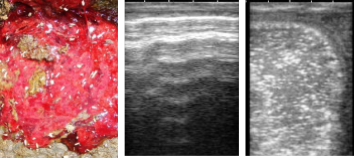

●妊娠鑑定

授精後可能な限り早く(授精後26日より超音波検査を実施)妊娠鑑定ならびに双胎妊娠診断,早期胚芽死滅(EED)を摘発し、繁殖リスクを最小限に留めます。

双胎妊娠